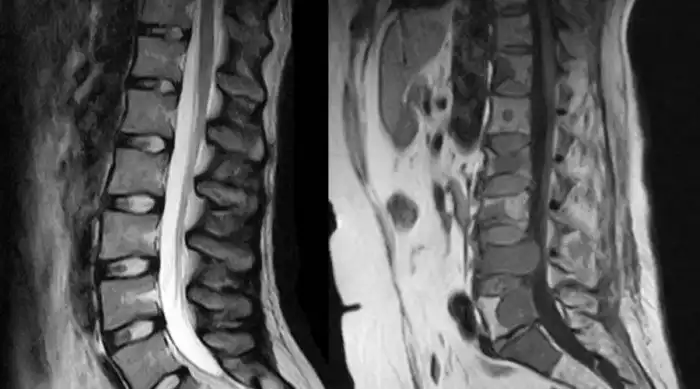

Телу приходится искать какую-то амортизацию при ходьбе. Довольно быстро развивается искривление позвоночника, лордоз, кифоз и сколиоз.

Под удар попадают и внутренние органы. Сдвинутые с места позвонки влияют на работу сердца, сдавленная диафрагма приводит к возникновению одышки. Страдает кишечник. Хуже всего, что искривление позвоночника может пережать нерв — грубо говоря, плоскостопие легко приводит к инвалидности даже молодого человека.